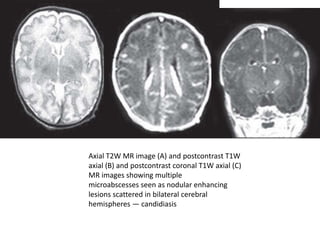

Imaging Findings

• On CT scan, the microabscesses and

granulomas typically show enhancement.

• On MR imaging, the hypointense to

isointense signal on T2-weighted images may

be helpful in distinguishing fungal granuloma.

A target appearance has also been described

in candidal abscess, which on T2-weighted

images shows a well-delineated hypointense

area surrounded by a hyperintense rim.

Axial T2W MR image (A) and postcontrast T1W

axial (B) and postcontrast coronal T1W axial (C)

MR images showing multiple

microabscesses seen as nodular enhancing

lesions scattered in bilateral cerebral

hemispheres — candidiasis